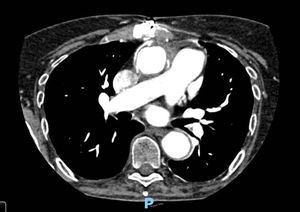

Our patient received voriconazole (400mg every 12h loading dose, followed by 200mg every 12h) combined with caspofungin (70mg/day loading dose, then 50mg/day) for 10 days, followed by voriconazole monotherapy. A CT of the thorax, brain, and paranasal sinuses did not show signs of Aspergillus spp. infection. Two serum galactomannan assays, performed 7 days apart, were also negative. Serum β-d-glucan (BDG) determination was not performed. A follow-up TTE was informed as normal, and a chest CT angiography performed three months later did not show new aneurysms or mechanical complications associated to the aortic tubular prosthesis (Fig. 3). Antifungal treatment was stopped two years later.